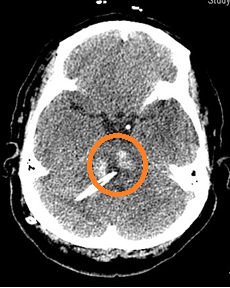

经过前期充分准备,手术如期开台。该手术由神经外科副主任医师黄云峰主刀。通过头颅CT扫描定位,黄云峰精密规划了最佳穿刺路径,确定手术入路,做到既能直达血肿腔,又能避开重要的血管及神经,不对周围的脑组织功能产生影响。随着引流管的精准置入,暗黑色的脑干淤血随引流管顺利流出,监护仪上患者的生命指征始终保持平稳。手术历时90分钟,这场与死神博弈的手术最终在神经外科手术团队、麻醉医生以及麻醉手术科护理团队的高效配合下获得了成功。

图为术后CT,引流管位置精确到位,提示颅内血肿清除彻底